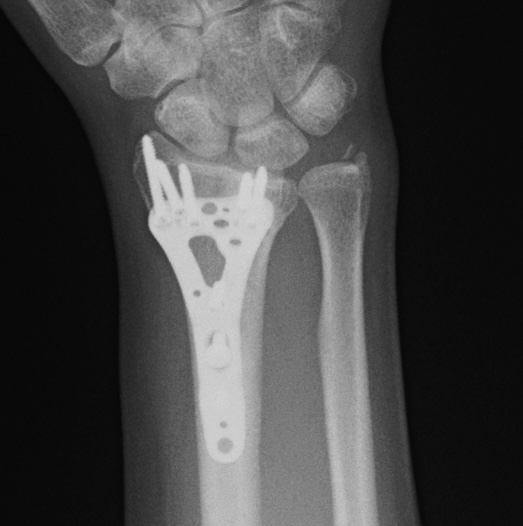

Клинический случай: внутрисуставной перелом дистального метаэпифиза лучевой кости — после операции

Контрольный осмотр и ранний послеоперационный результат.